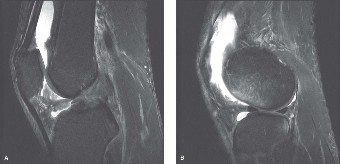

CASE 2 An 18-year-old soccer player injures her knee during competition. She r…

CASE 1 A 22-year-old, female jogger presents complaining of right knee pain. She describes an insidious onset…